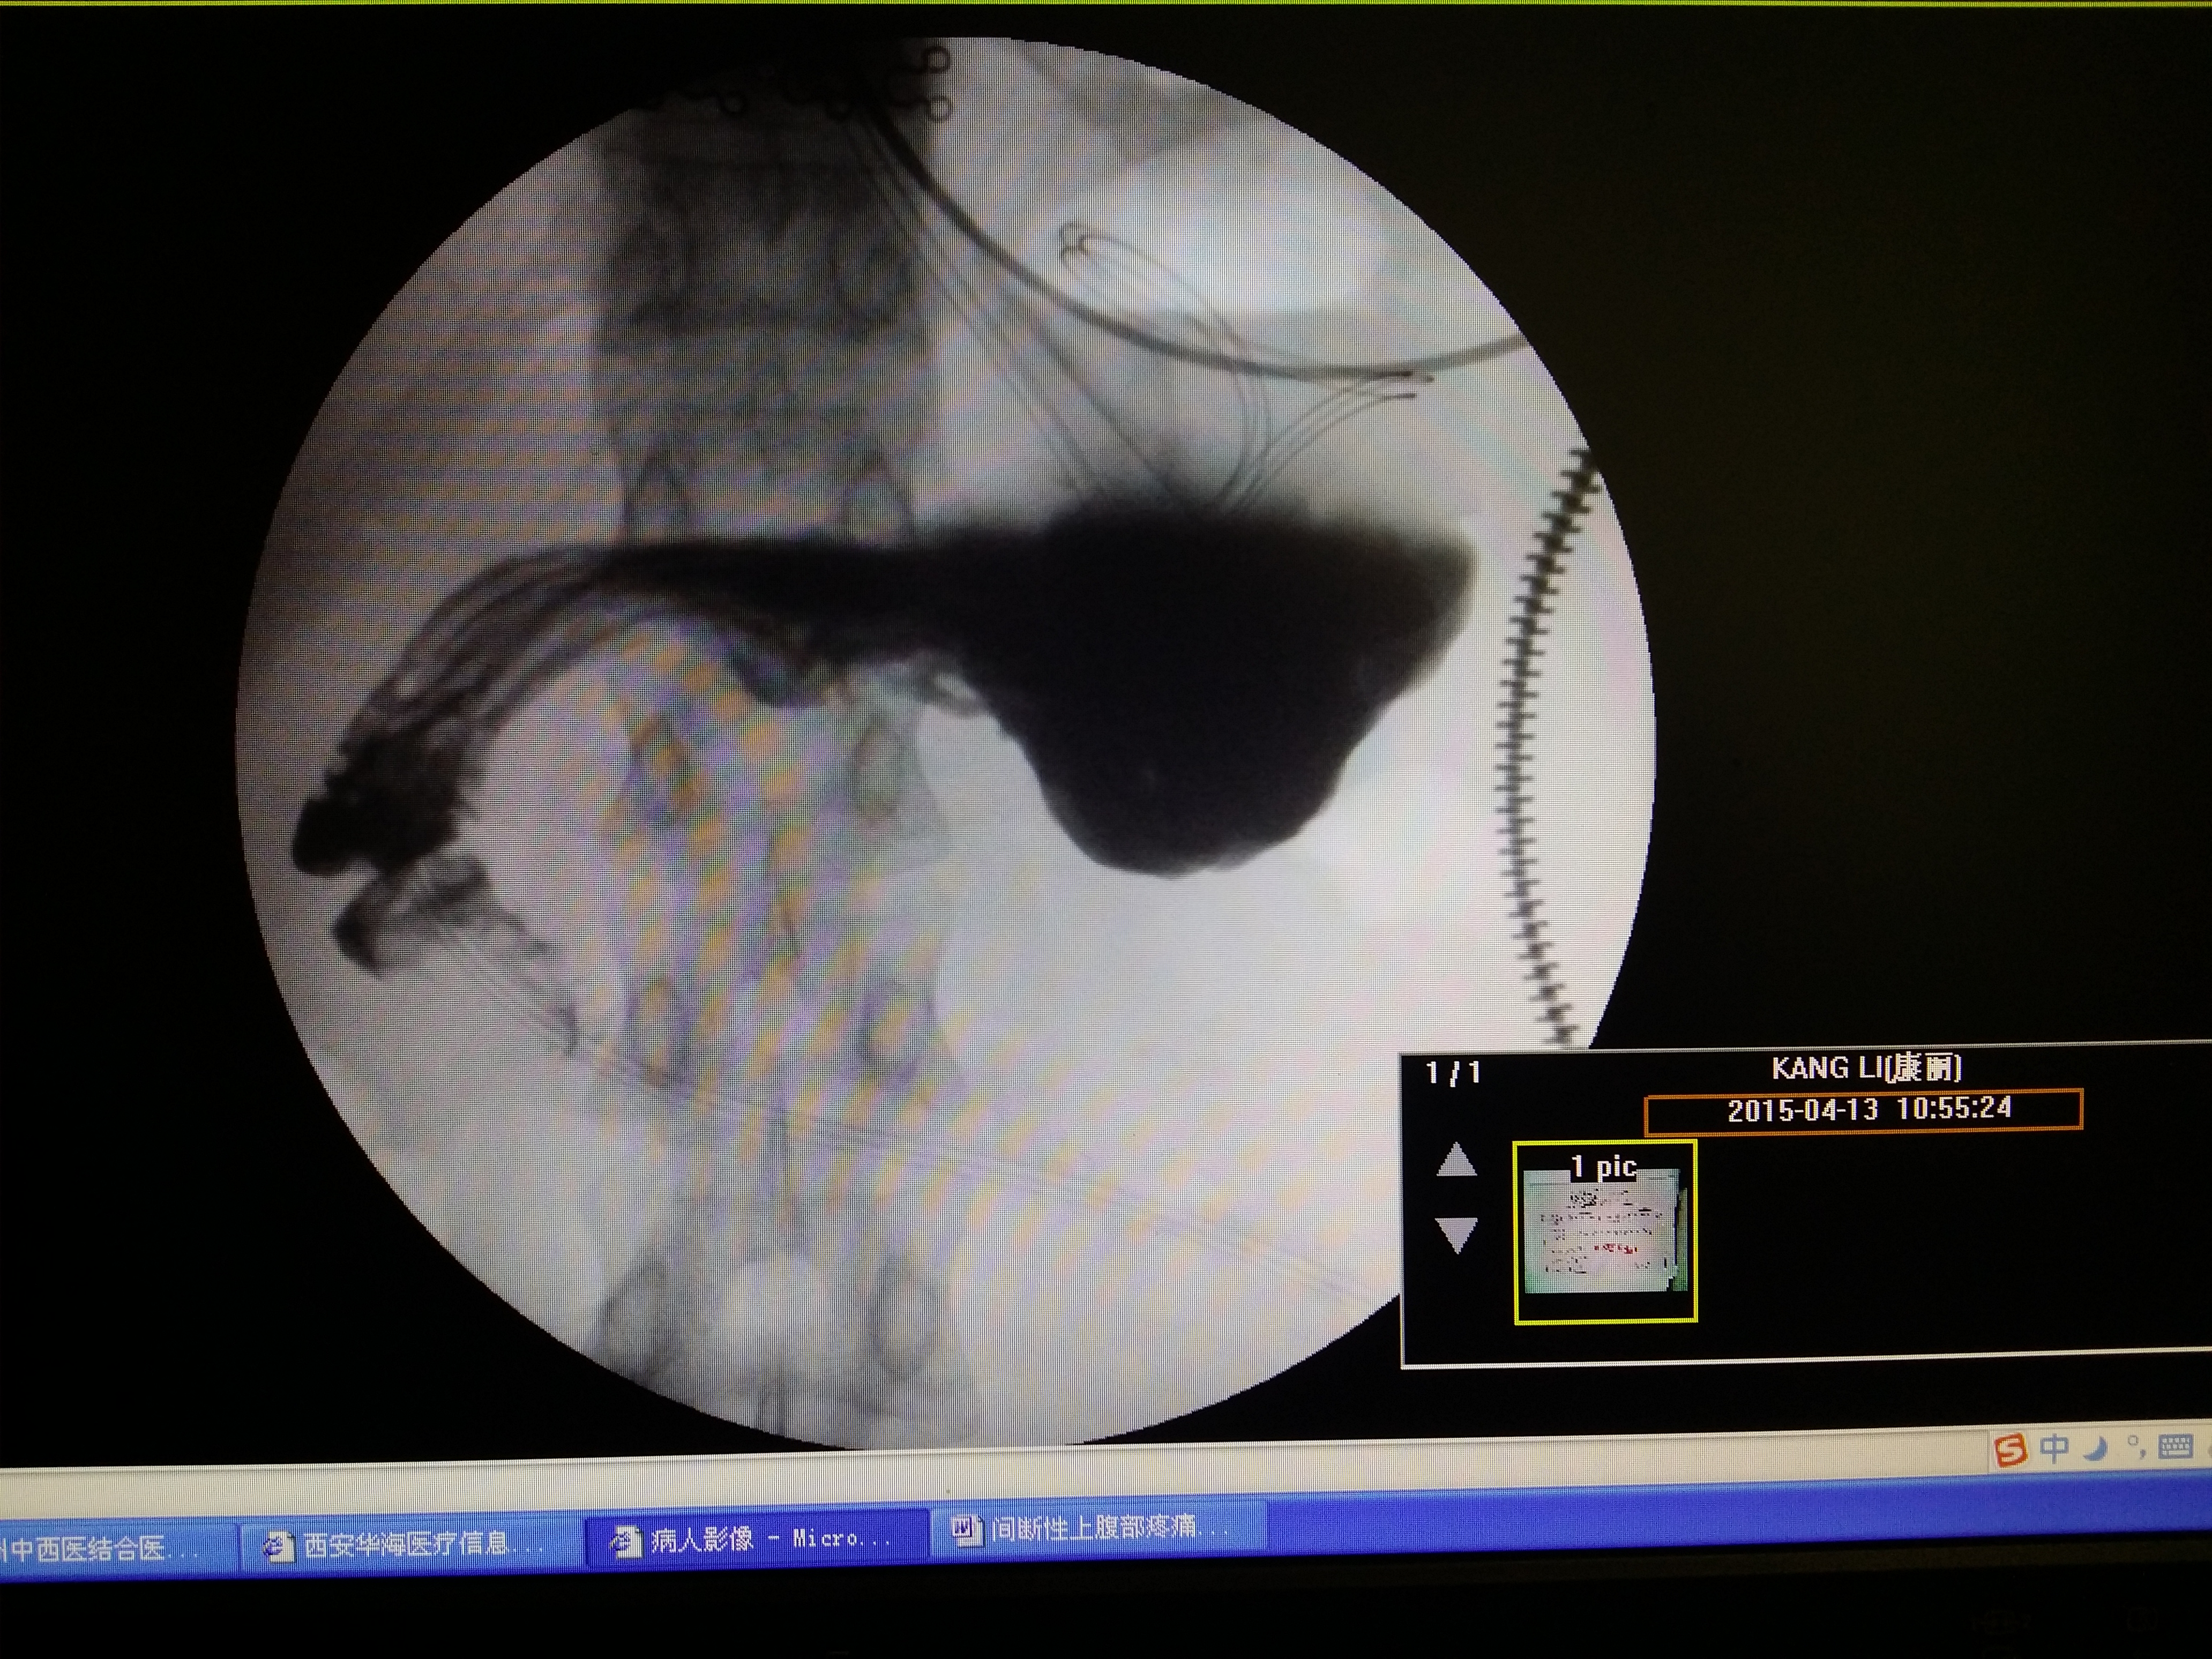

术后胃瘫医案附患者治疗前后消化道造影对照

图片尺寸4128x3096